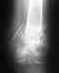

Операция прошла в Москве... поставили американскую шпильку не знаю как правильно назвать На Шейку бедра.... Прошло 4 месяца мы из Ташкента. Поставили диагноз такой "Саркома или просто мозоль" как так?? Помогите!!!